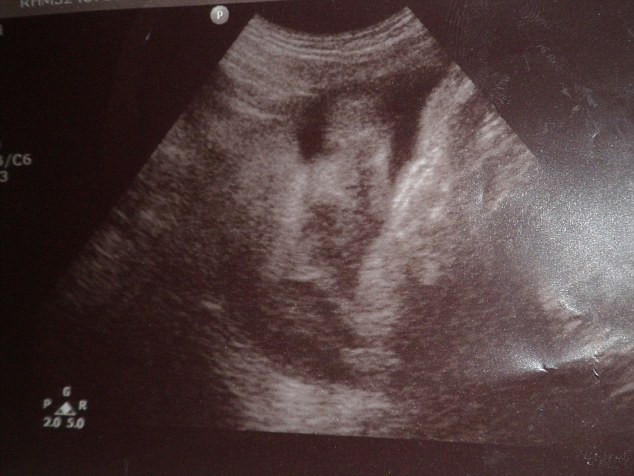

Femeia, care este instructoare de fitness, a inceput sa se simta rau, sa oboseasca in timpul exercitiilor si chiar a simtit o umflatura in abdomen. Allison s-a temut ca nu cumva sa aiba cancer si a mers de urgenta la spital.

Medicul a anuntat-o ca este insarcinata si ca o sa nasca in maximum 2 saptamani.La 12 zile de la control, ea a adus-o pe lume pe Sophie, o fetita sanatoasa si vesela.